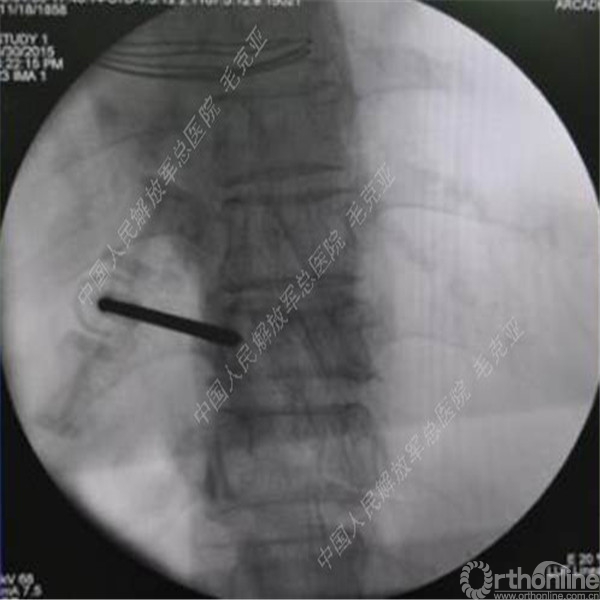

毛克亚:新型弯角椎体增强装置的研制与临床应用研究

导语:随着社会老龄化的不断加速,骨质疏松性椎体压缩骨折作为一种普遍存在的老年骨科疾病已经成为现今骨科界的一个热点话题。传统的保守疗法治疗效果不佳,而现有的椎体增强技术又具有多种风险和缺陷。针对这种现状,中国人民解放军总医院毛克亚教授提供了一种新的解决方法。